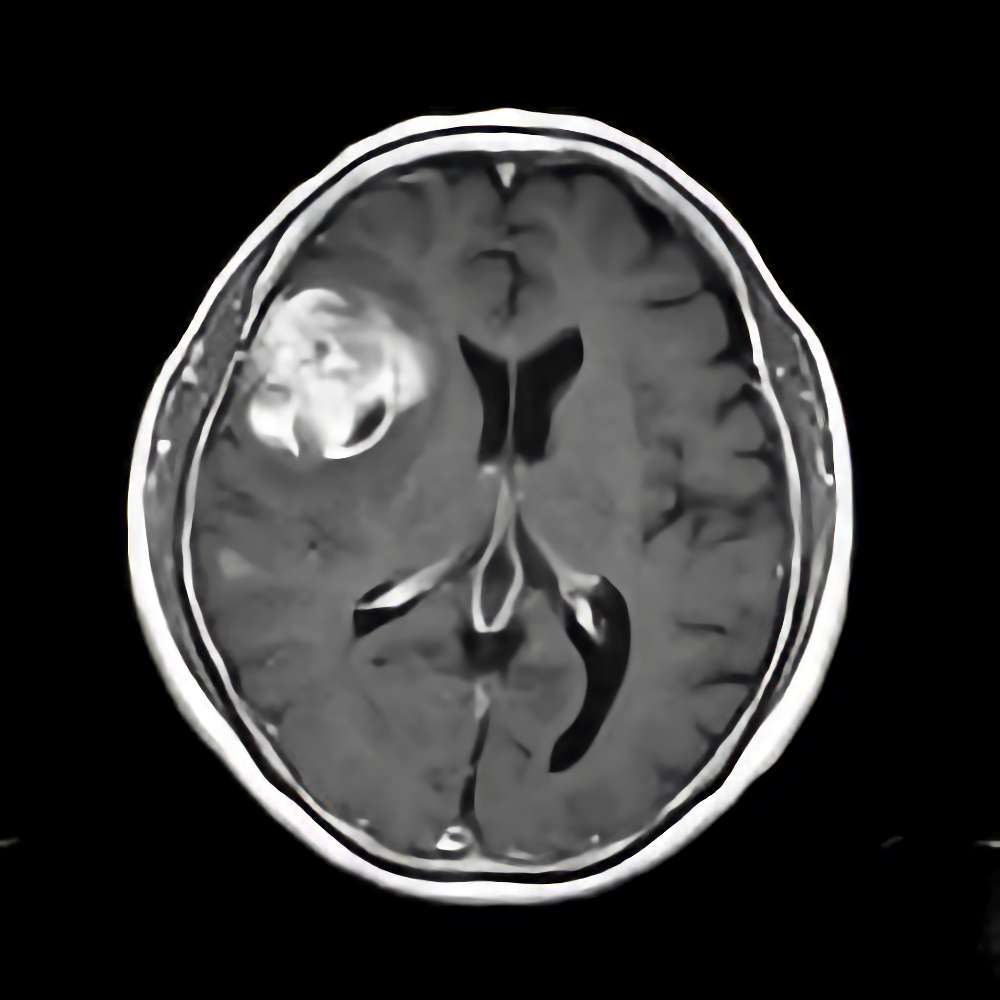

側頭葉膠芽腫

No.’16_129 手術前1

No.’16_129 摘出 前

No.’16_129 摘出 後